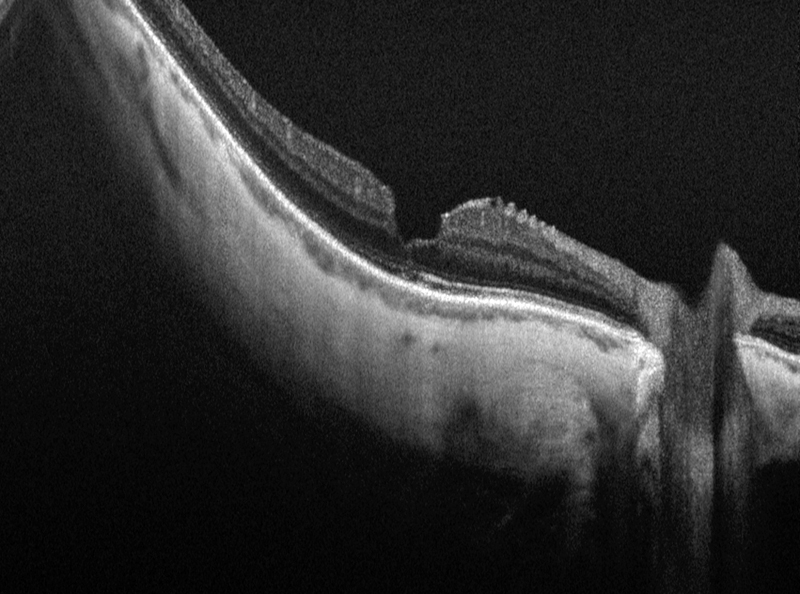

Posteriormente, la serie de Wakabayashi

et al.24 apuntaló la relación entre la alteración en la línea OS/IS, la alteración en la MLE y la mala agudeza visual postoperatoria (

Figura 5). Ahondando en esta relación, describió el fenómeno de restauración de la línea OS/IS, que sólo ocurrió en aquellos pacientes que presentaban una MLE íntegra, y que explicaría la progresiva recuperación de la agudeza visual de forma lenta en los casos con mácula afecta (

Figura 6).

Figura 5. Alteración de la membrana limitante externa (MLE) y la capa de fotorreceptores (OS/IS) subfoveal (Zeiss Cirrus SD-OCT).

Figura 6. Reparación de la capa OS/IS con membrana limitante externa íntegra (Zeiss Cirrus SD-OCT).